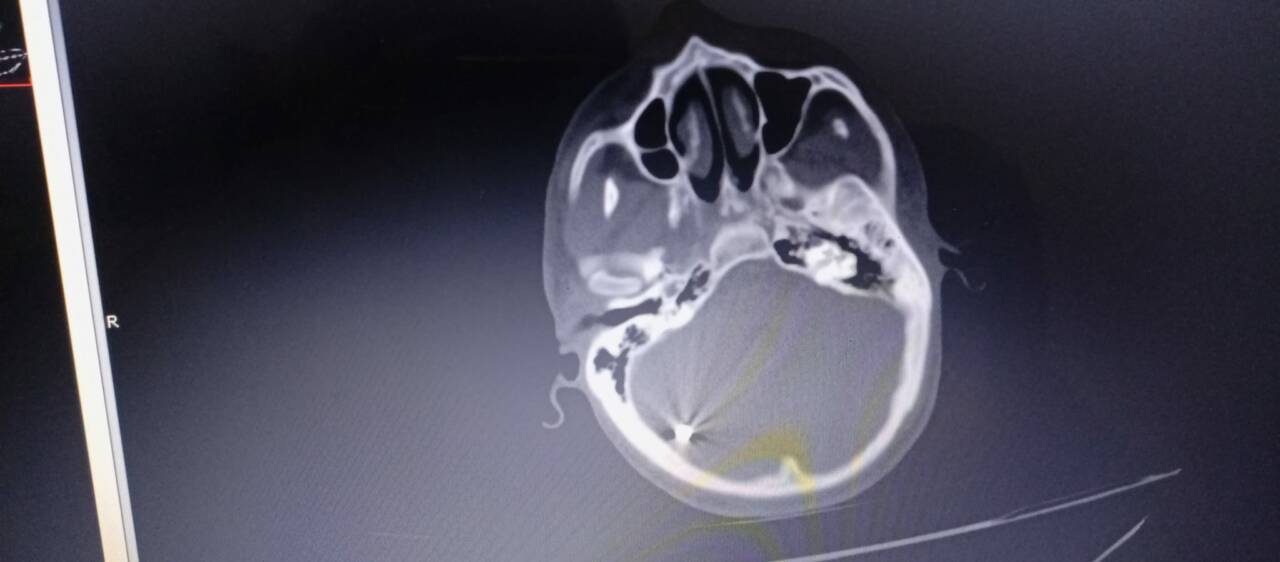

“Beyninde metal parçalar tespit edildi”

Adıyaman Eğitim ve Araştırma Hastanesi’nde yapılan tetkiklerde Ahmed Elhasan’ın beyninde ve kafatasında metalik yabancı cisimler tespit edildi.

Hastane raporlarına göre, hastada bombadan kaynaklı konvülziyon, hemipleji ve quadriparezi (kısmi felç ve kas kontrolü kaybı) gibi ciddi nörolojik sorunlar bulunduğu ve acil ileri tedaviye ihtiyaç duyduğu belirtildi.